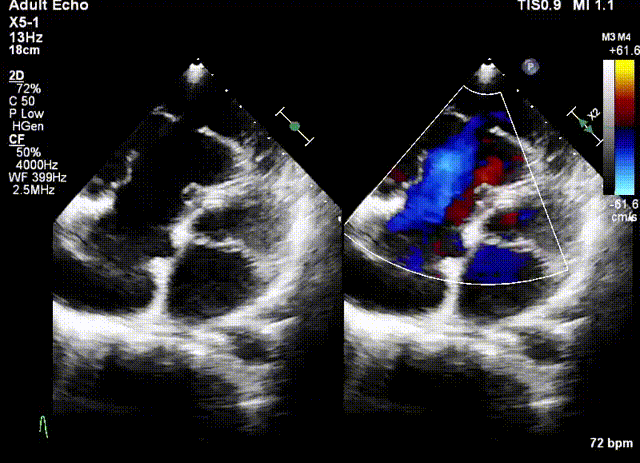

術前超聲

該例患者為79歲女性,NYHAⅢ級,心衰癥狀顯著,藥物(大劑量利尿劑)治療9個月后仍出現頑固性踝關節水腫。術前超聲心動圖提示三尖瓣重度反流(5+),右房右室擴大,三尖瓣瓣環擴張合并嚴重三尖瓣葉栓系,TAPSE 1.9cm,gap 23.2mm,PASP 30~35mmHg,LVEF 58%。